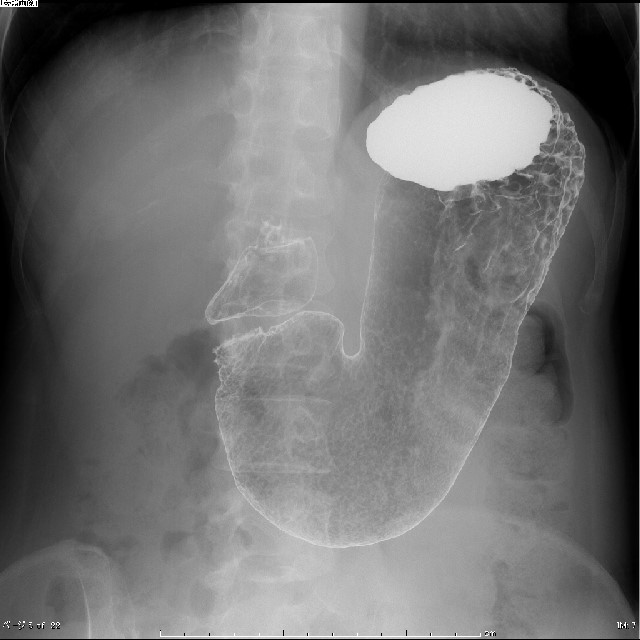

X線TV検査

X線TV検査はX線を使用し体の透視像をリアルタイムに観察することができる検査です。胃のバリウム検査をはじめ、消化管(食道、小腸、大腸)の観察、整形領域では骨折や脱臼の整復等を行っています。